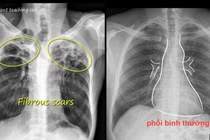

Lao phổi là bệnh có thể để lại di chứng, dẫn đến những vấn đề sức khỏe lâu dài dù việc chữa trị căn bệnh này đã có nhiều tiến bộ. Ước tính có khoảng ⅕ số người sau điều trị bệnh lao phổi gặp di chứng.

Chăm sóc và theo dõi sau khi hoàn thành điều trị lao thường bị bỏ qua. Sau khi hoàn thành điều trị, mặc dù cơ thể đã tiêu diệt hoàn toàn vi khuẩn lao nhưng vẫn có thể để lại những triệu chứng hoặc di chứng do lao hoặc thuốc.